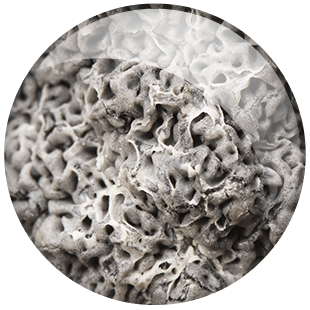

A gray sticky mucus has clogged your blood sugar drain.

And yet, as you read this, a gray sticky mucus is blocking up your drain.

This clog is sending sugar back into your blood. It pushes your blood sugar levels higher.

A little-known ‘gray sticky mucus’ is clogging up their body’s Blood Sugar Drain.

Excess sugar should get drained. But instead, that clog sends it right back to your bloodstream. Your blood sugar levels go sky high.